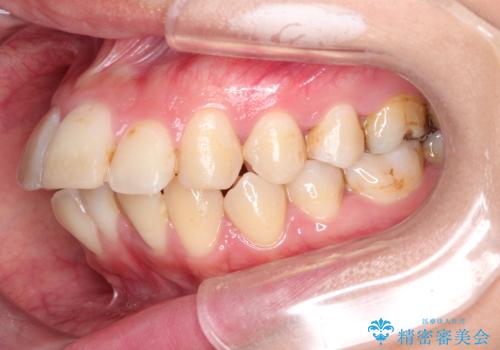

- 口元が出ていることを気にされて来院されました。精密な検査の結果、歯列全体のスペースが不足していることが判明。患者様のご希望である「口元を下げたい」というご要望を叶えるため、上下左右の小臼歯を抜歯し、そのスペースを利用して前歯を奥へ移動させる治療計画を立案しました。また、仕事上、目立つ矯正装置を避けたいというご希望から、上顎に裏側矯正、下顎に表側矯正を組み合わせたハーフリンガル矯正を提案しました。

今回の矯正治療では、口元を大きく下げるため、上下左右の小臼歯を抜歯しました。装置には、上顎は歯の裏側に装着する裏側矯正(舌側矯正)を、下顎は透明で目立ちにくい審美ブラケットを使用するハーフリンガル矯正を選択。これにより、治療中も他人の目を気にすることなく、ストレスなく過ごしていただけました。抜歯によってできたスペースを有効活用し、歯列全体を後方へ移動させることで、口元の突出感を解消。治療の結果、口元がすっきりと整い、自信のある美しい横顔を獲得していただけました。